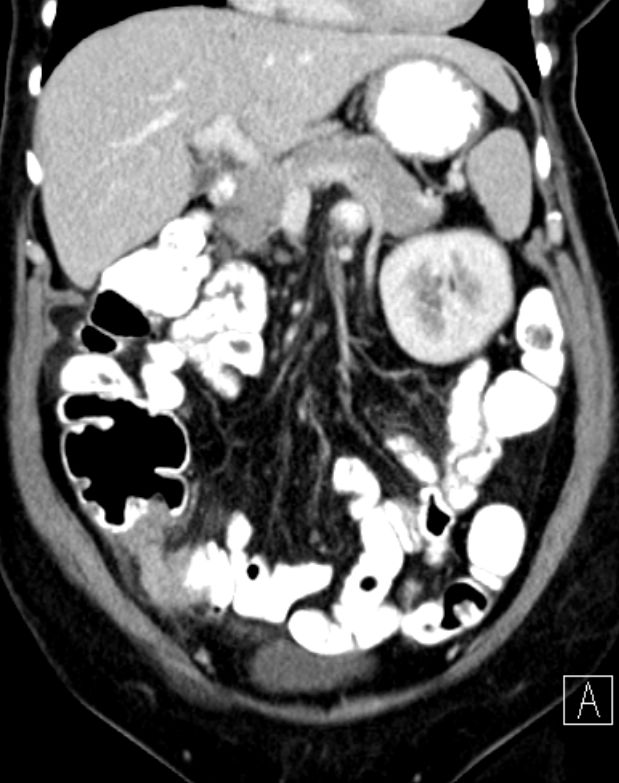

66-jährige Frau mit einem Appendixtumor. Histologisch niedrig maligne muzinöse Neoplasie.![]() |

![]() |